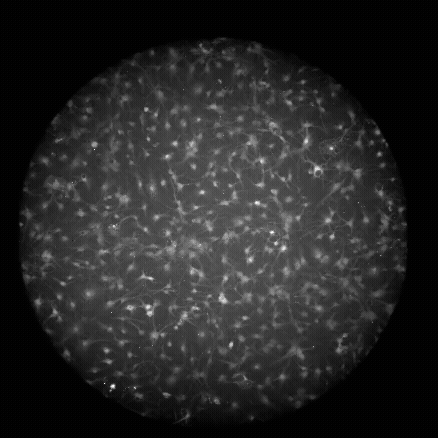

Les astrocytes des rats implactent la lumière, ce qui indique leur activité.

Les astrocytes étaient considérés comme des aides, aidant au travail de grognement dans le cerveau. Ces cellules en forme d'étoile nettoient les déchets entre les cellules nerveuses, servent de barrières qui empêchent les menaces nocives du cerveau et guident les cellules nerveuses pour se connecter les uns aux autres.

De plus, ces cellules sont partout. Les estimations varient, mais les astrocytes peuvent constituer environ 20% des cellules cérébrales, explique Kevin Guttenplan, co-auteur de l'une des nouvelles études et neuroscientifiques de l'Oregon Health and Science University à Portland. Les astrocytes se développent jusqu'à ce qu'ils rencontrent un autre astrocyte et forment des milliers de connexions avec d'autres cellules, «ce qui signifie que chaque millimètre carré du cerveau se trouve dans le domaine d'un astrocyte», explique Guttenplan.